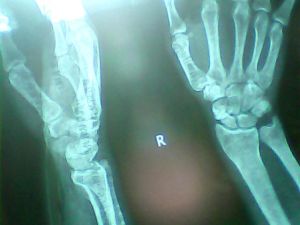

一般骨折三周之內的分為新鮮骨折,而三周以後的稱為陳舊性骨折。

骨的完整性或連續性被中斷或破壞。由外傷引起者為外傷性陳舊性骨折;若骨骼本身因某種疾病,如腫瘤、炎症、內分泌平衡失常等,而堅固性受影響,即使在極輕微的外力下,也可以引起陳舊性骨折,這種陳舊性骨折稱為病理性陳舊性骨折。